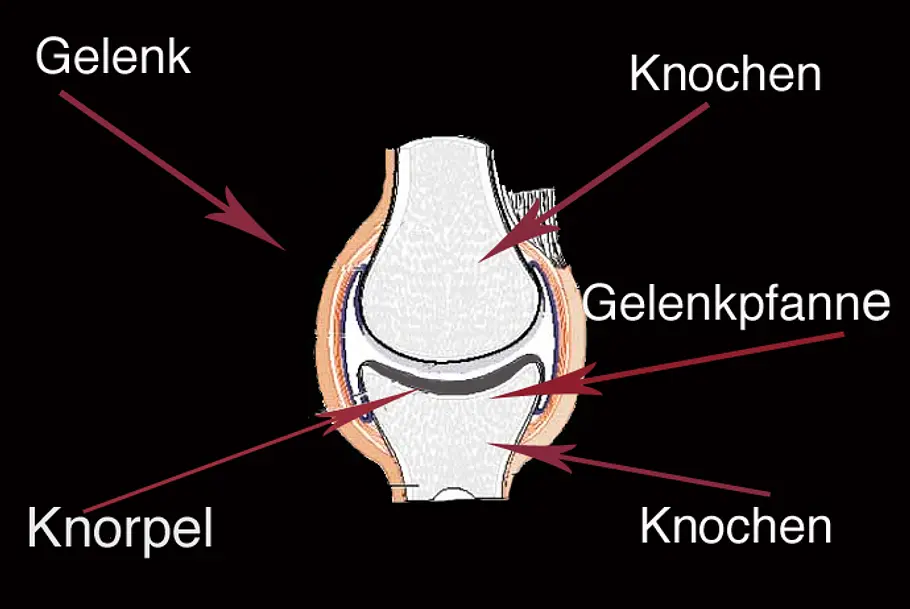

Wenn sich jedoch, zum Beispiel durch einen Unfall oder eine Entzündung, der Knorpel – oder kleine Teile des Knorpels – lösen, dann spricht man von sogenannten "freien Gelenkkörpern".

Der „Gelenkkörper", also der Knorpel, ist nun nicht mehr mit dem Gelenk verbunden. Das Problem: Die abgelösten Knorpel reiben nun bei jeder Bewegung zwischen Knochen und Gelenkpfanne – oder blockieren sogar die Bewegung. Das ist nicht nur sehr schmerzhaft, sondern kann auch dauerhafte Schäden am Gelenk verursachen!